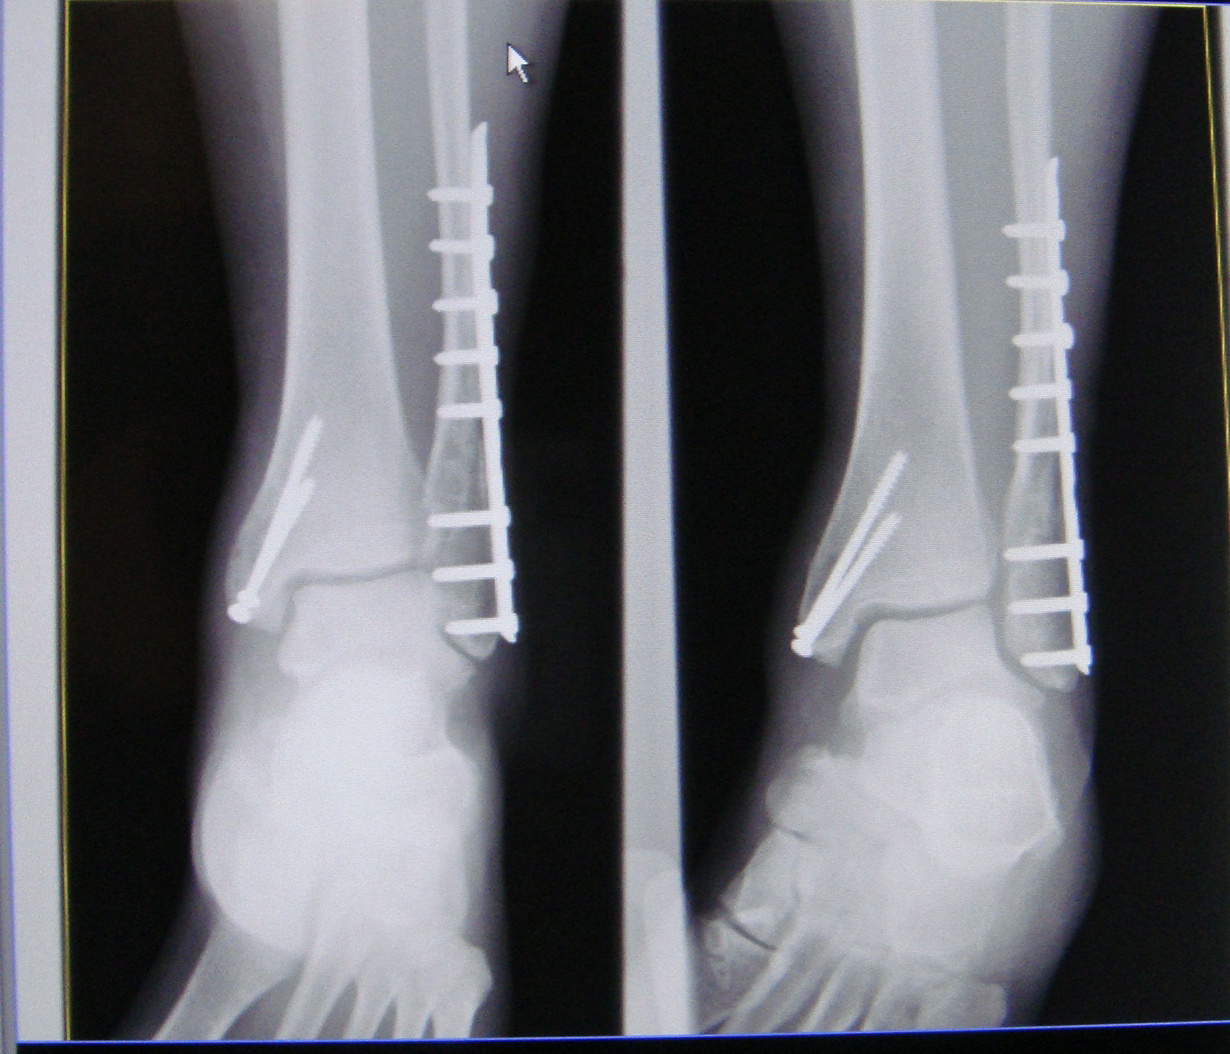

AP and ankle profile radiographs showing the trimalleolar dislocation Where Is The Trimalleolar Located When you have a trimalleolar fracture, you've broken three bony sections at the end of your lower leg bones: These consist of the lateral malleolus, which is at the end of. These bones create a triangle in your ankle. The fractures involve the medial malleolus, the posterior aspect of. The medial, lateral and posterior malleoli. In a trimalleolar ankle fracture,. Where Is The Trimalleolar Located.